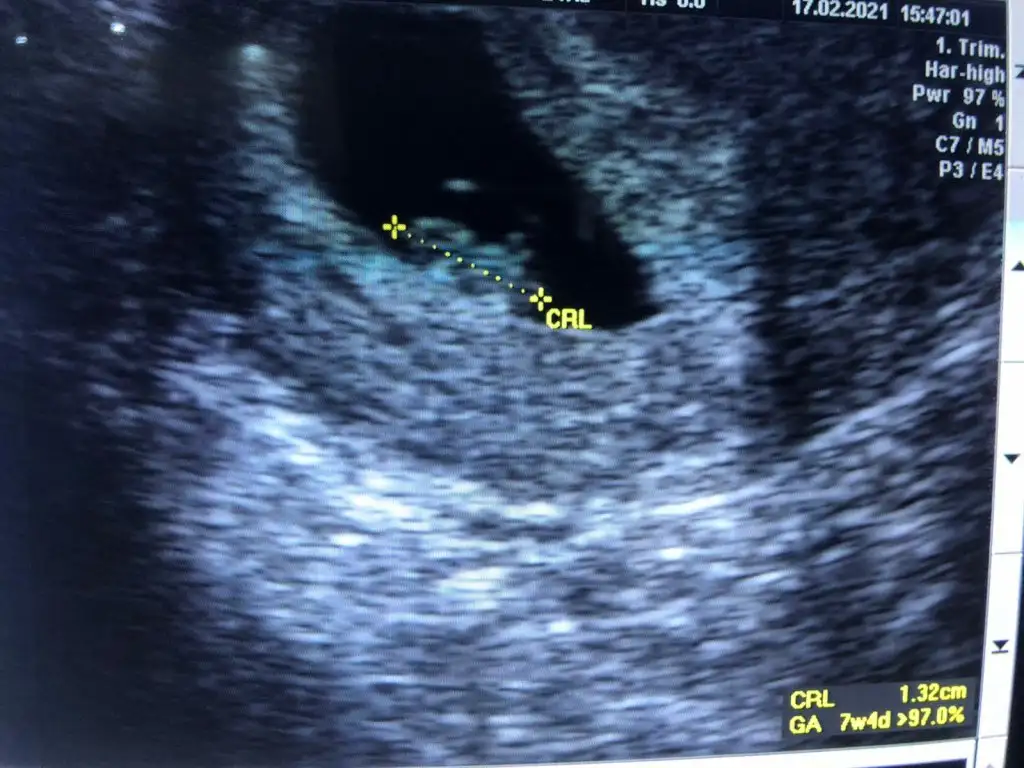

• WhatsApp Image 2021-02-13 at 12.55.22 (2).webp

WhatsApp Image 2021-02-13 at 12.55.22 (2).webp

18 KB · Görüntüleme: 79